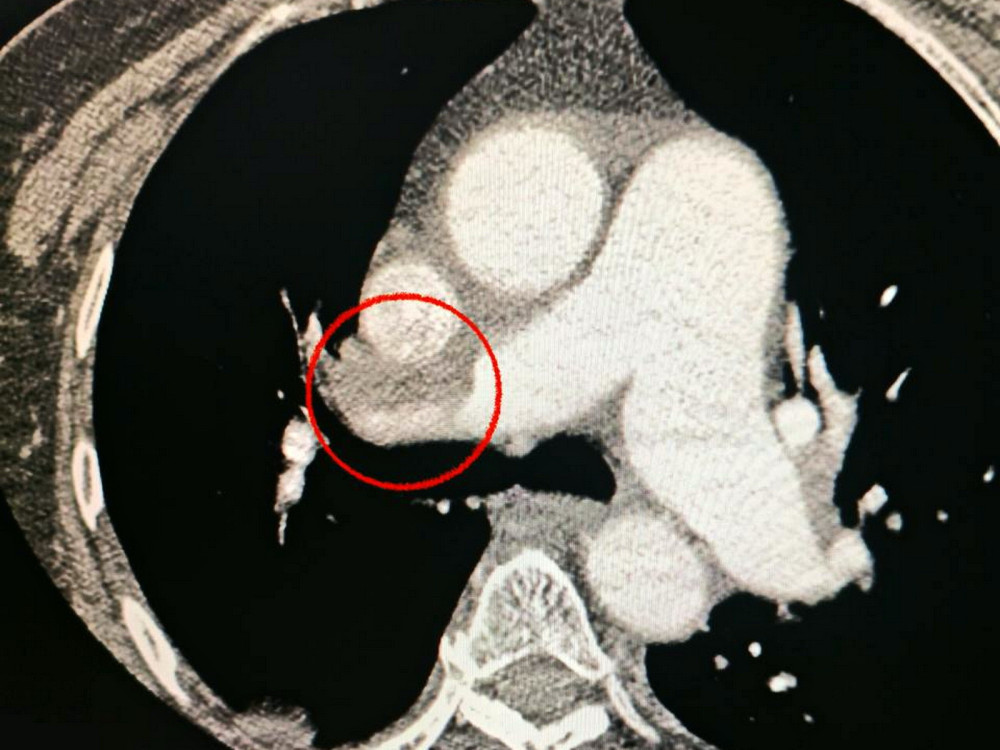

Пацієнтка, одеситка, була госпіталізована з важким гострим мозковим інсультом. Під час комп'ютерної томографії медики виявили закриття середньої мозкової артерії.

Також лікарі помітили, що у жінки виникають проблеми з диханням, тому провели додаткове обстеження легень. Виявилося, що у неї також є тромбоемболія легеневої артерії.